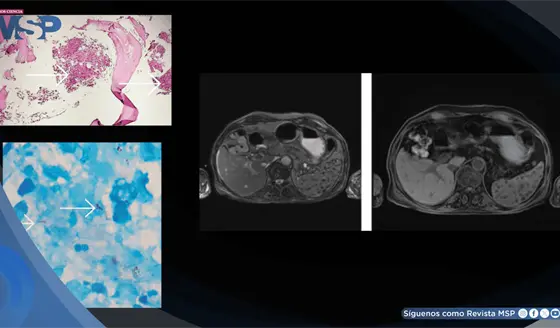

Tuberculosis extrapulmonar infiltró la médula ósea y provocó pancitopenia severa en adulto mayor